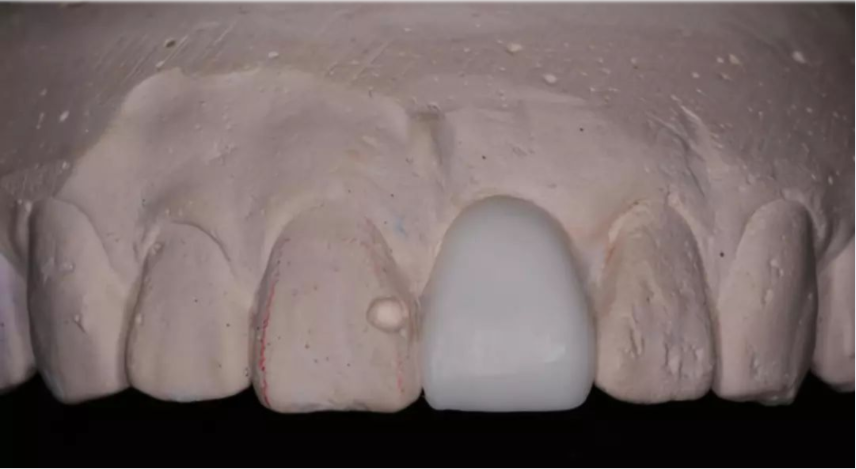

術(shù)前制取參考模型,排美學蠟型,實現(xiàn)以美學修復(fù)為導(dǎo)向的種植

患者佩戴此U型管開合拍攝CBCT,其中可以獲得缺牙區(qū)修復(fù)體的切端及齦緣等信息

患者佩戴此U型管開合拍攝CBCT,U型管中的放射標記點清晰顯影

設(shè)計軟件中,選擇適合的種植體

根據(jù)修復(fù)體形態(tài),軸向以及骨量將種植體放置最適合的位置